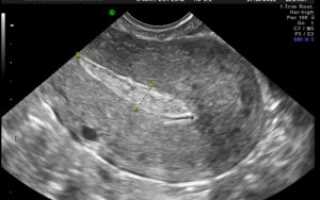

Гинеколог выявляет мягкую консистенцию органа при осмотре. Подтверждают развившийся негативный процесс клинические и биохимические анализы мочи и крови, трансвагинальное УЗИ (ультразвуковое исследование).

Проводится визуальный осмотр шейки матки и пальпация. Внутренний зев ее будет расширен, плодный остаток в наличии. УЗИ определит его объем и локализацию, а также общее состояние репродуктивных органов. Биохимический анализ крови расскажет о функционировании органов и систем пациентки.

При неполном аборте беременность больше не подтверждается различными тестами, поэтому примерно через неделю после отторжения плодного яйца необходимо сделать УЗИ, чтобы удостовериться, что в матке нет остатков эмбриональной ткани. Если остатки плодного яйца после медикаментозного прерывания беременности обнаружены, следует вовремя начать лечение.

Послеоперационное лечение обычно заключается в том, что проводится обследование гормонального фона, а также назначается антибактериальная терапия. Нужны регулярные контрольные гинекологические осмотры – берутся мазки на микрофлору и назначается УЗИ органов малого таза.

Что делать? Лучше этот вопрос заранее обговорить с врачом. По стандартным рекомендациям УЗ-исследование после аборта выполняют на 10-14 день, но если это сделать через 5-7 дней, то есть возможность вовремя заметить признаки неполного аборта и назначить лекарственные средства.

Через 2–3 дня женщина вновь должна посетить врача. Гинеколог осмотрит пациентку, оценит ее состояние. Будет проведено УЗИ, результат которого покажет эффективность проведенной процедуры. Если выкидыш при помощи медикаментозных средств не произошел, женщине понадобится чистка. Беременность после фармаборта сохранять нельзя.

При появлении первых симптомов, вызывающих опасение, женщина должна обратиться в больницу. Основными методами диагностики состояния являются гинекологический осмотр и УЗИ.